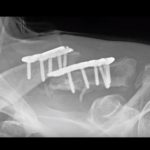

Posterior Malleolar Fracture for FRCS Orth

Courtesy: Rajesh Kakwani, FRCSOrth, Northumbria Health Care, UK